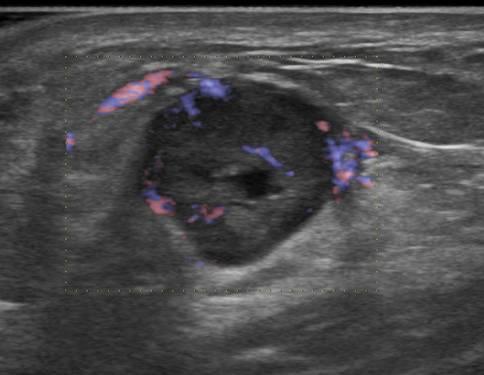

Ung thư vú

Ung thư vú - Ảnh 4

» Thông tin: Nữ giới – 54 tuổi.

» Lâm sàng: Khối tuyến vú.